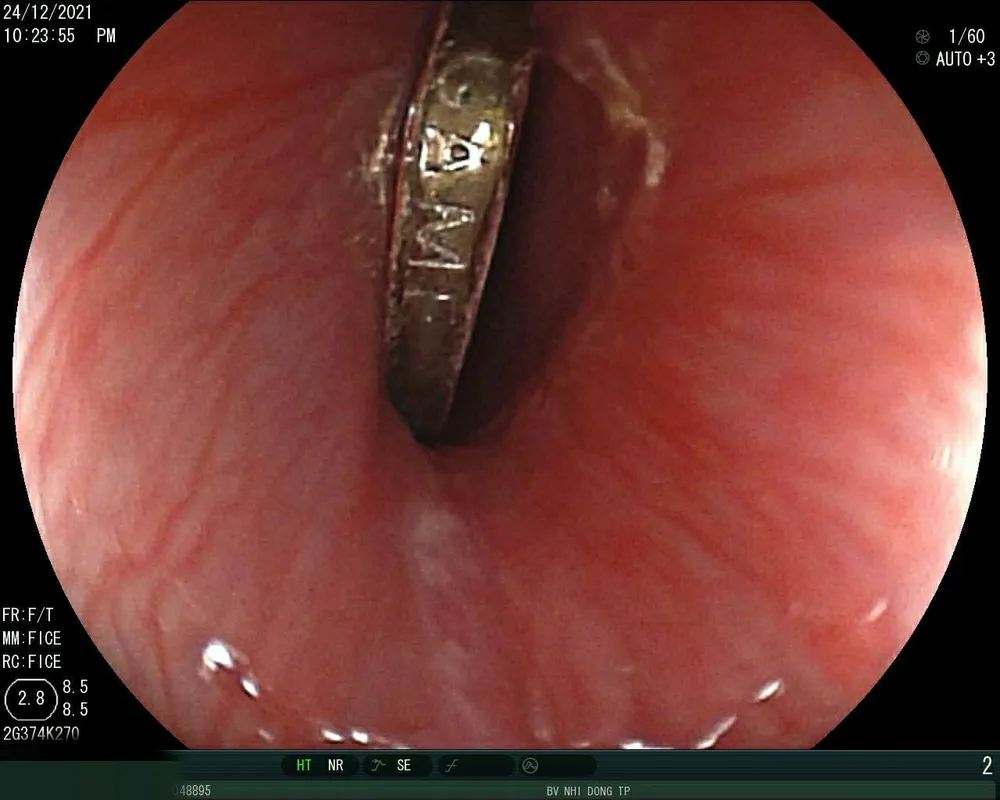

Đồng xu đồ chơi bé trai nuốt phải đang chặn 1/3 thực quản. Ảnh: BVCC

Bé được các bác sĩ gây mê, nội soi gắp kịp thời đồng xu đang chặn 1/3 thực quản kịp thời.